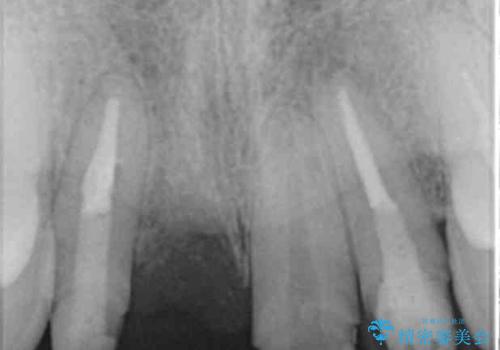

CT撮影を行った結果、右上前歯は吸収が進み抜歯が必要な状態です、

抜歯をせず放置すると、より吸収が進み臨在する歯にも悪影響を及ぼしてしまう可能性が考えられます。

上顎4前歯は、根管治療の既往があり、虫歯も見られたことからブリッジによる治療で審美性の回復を行うとともに臨在歯の虫歯もセラミック治療を行っていきます。